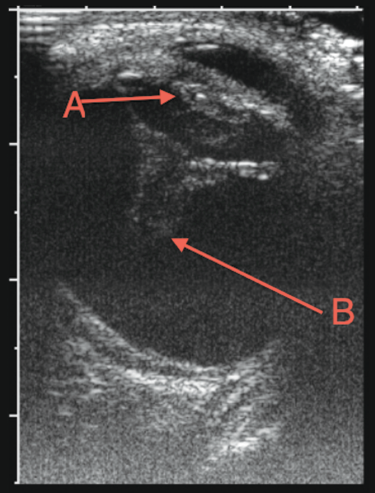

On physical examination, the boy’s vital signs were normal, his height was at the 25th percentile, and his weight was at the 75th percentile. Examination showed a red right eye with a complete hyphema obscuring the pupil (A). Pupillary size and reaction were difficult to assess in the right eye. The conjunctiva was injected, and the patient was unable to see light or hand movements in the affected eye. No conjunctival hemorrhage or discharge was noted, and there was neither proptosis nor pain with eye movements. The left eye was entirely normal on examination, and the rest of his physical examination was unremarkable.

Results of laboratory evaluation, including complete blood count, basic metabolic profile, and coagulation studies, were within normal limits. An ultrasonogram of the right eye done by a pediatric radiologist showed blood in the anterior and posterior chambers, with lens displacement and retinal detachment (B).

Figure – Anteroposterior right-eye ultrasonogram showing blood in the anterior and posterior chambers, along with lens dislocation (A) and retinal detachment (B).